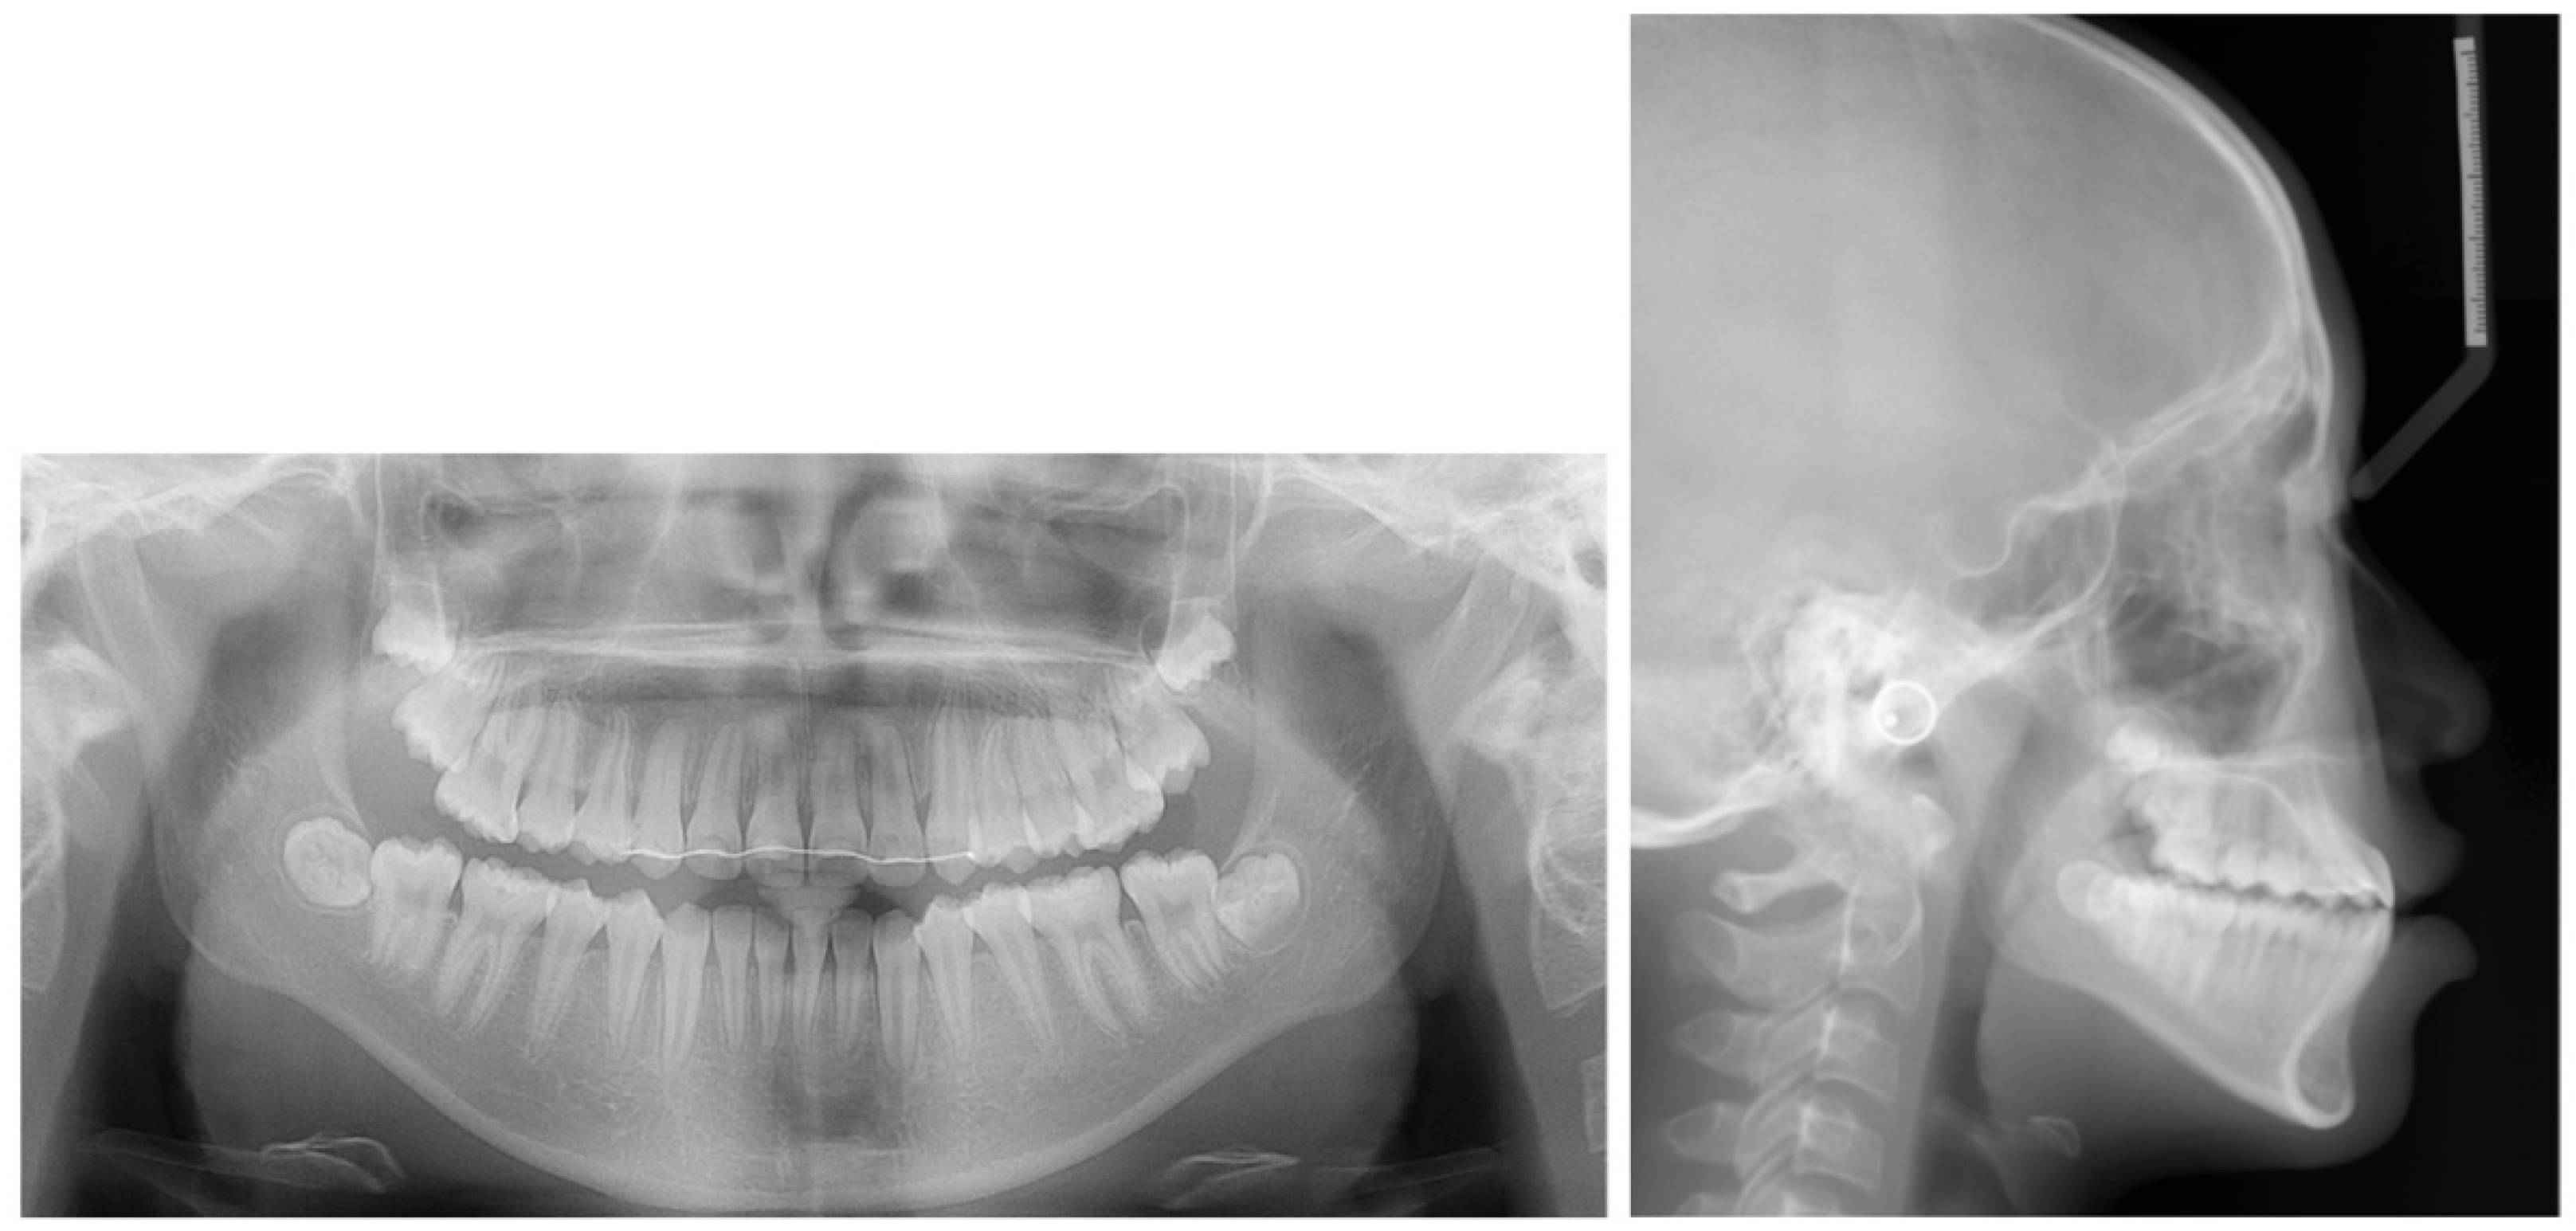

2.1. Diagnosis and Etiology

2.4. Treatment Progress